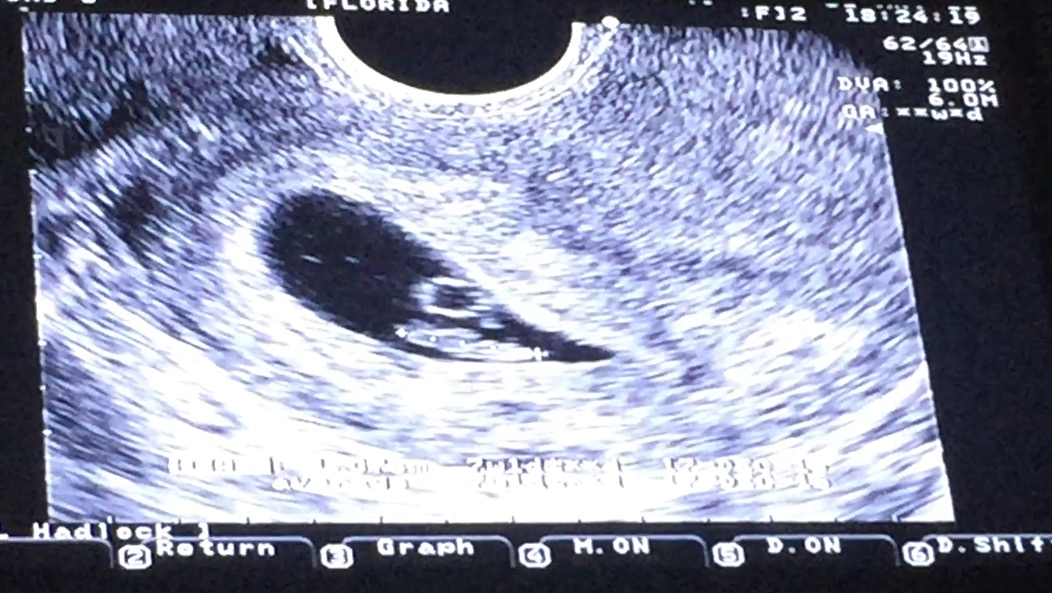

Attachment 31068 Can anyone guess my 7 week ultrasound pic based on Ramzi theory? This is transvaginal, thanks!